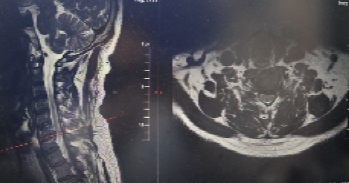

患者为 50 岁男性,3 个月前无明显诱因出现左上臂外侧、前臂背侧麻木胀痛,伴颈肩部酸痛不适,偶有行走不稳症状。在外院就诊时,颈椎 MR 检查提示 “颈椎生理曲度变直,颈椎增生,颈 6-7 终板变性,颈6-7椎间盘突出神经受压”,经保守治疗后症状无改善,为寻求进一步精准治疗来到我院。

入院后,骨科团队为患者进行了详细查体,发现其颈椎生理曲度变直,左侧颈肩部肌肉压痛阳性,左前臂背侧感觉减退,四肢肌力虽正常,但神经根受压症状明确,结合影像学检查结果,最终确诊为 “神经根型颈椎病”。考虑到患者保守治疗效果不佳,且症状已影响生活质量,患者较轻,团队经充分评估后,决定摒弃传统前路开放融合手术,采用后路微创内镜技术为其实施减压。